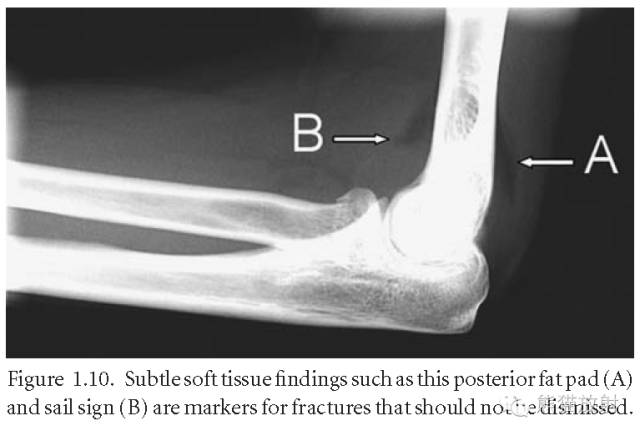

脂肪垫征(fat pad sign):又称帆船征(Sailing sign) 或八字征;细微的软组织表现是骨折的标志,不应漏掉。前后脂肪垫移位提示肘关节内的积血、积液改变,使关节滑膜、脂肪垫被推移,在侧位片上呈“船帆”状;虽然有时肘关节x片中看不到骨折线,但是出现前脂肪垫征时强烈提示有桡骨小头骨折。